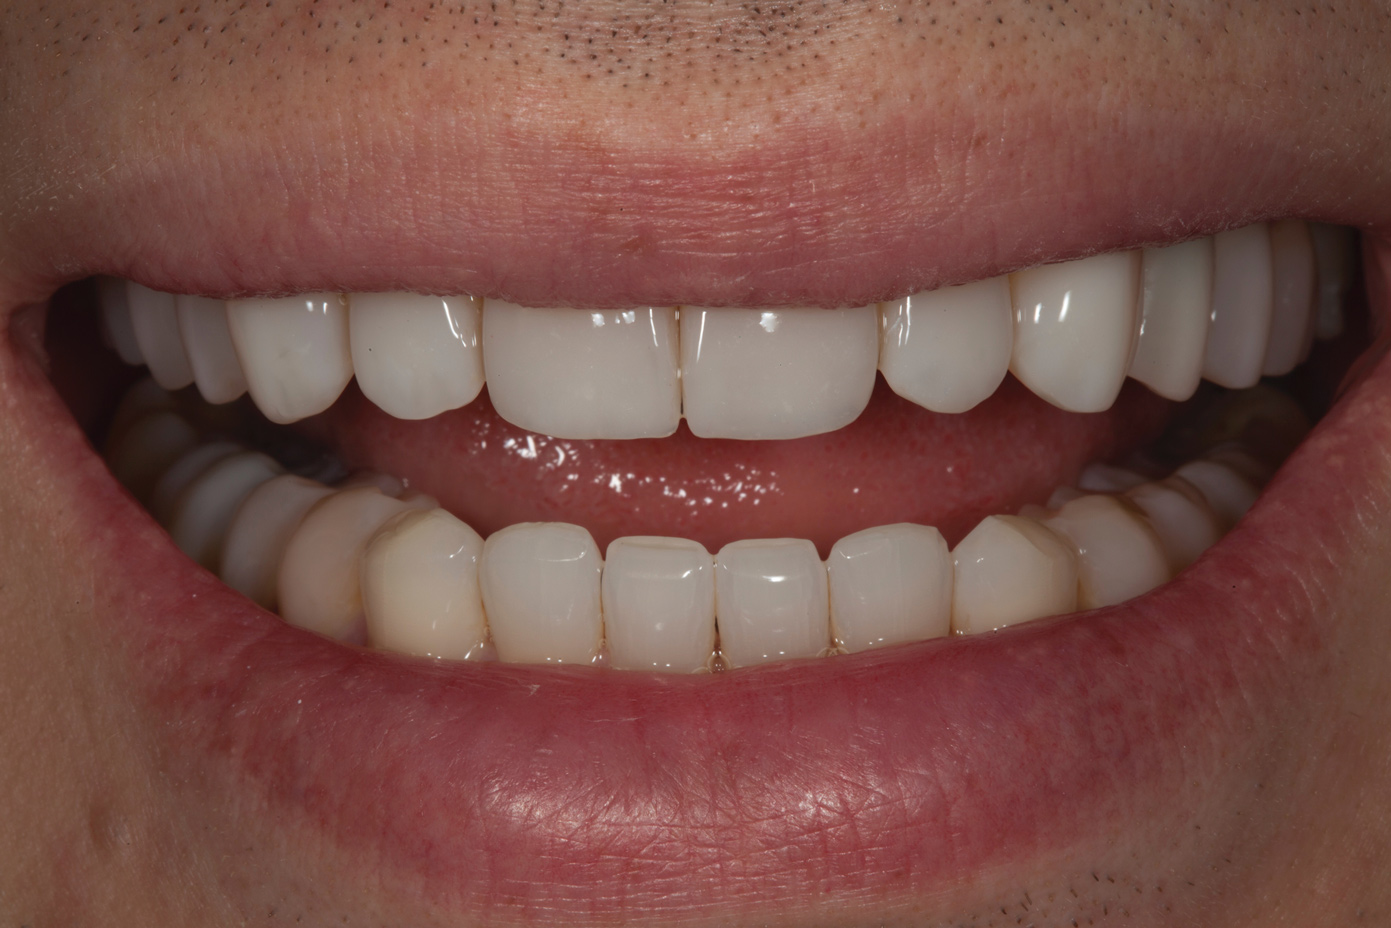

Fig 10. Postoperative smile photograph.

Figure 10

Following caries treatment and tooth preparation (Figure 6), teeth Nos. 4 through 13 were restored with direct composite veneers in stages (Figure 7 through Figure 9). Using a hybrid composite for the lingual shelf and dentin layer provides wear resistance and strength for the restoration.14,15 (The lowest wear rates for restorations and the opposing dentition occur with metal alloys, machined ceramics, and microfilled hybrid resin composites. Any adjusted and unpolished porcelain surface would elicit the most wear on the opposing teeth.11)After the composite veneers were finalized, a monolithic lithium disilicate crown was placed on tooth No. 12 during a subsequent appointment, and occlusal equilibration was carried out. Final photographs were taken a couple of weeks later (Figure 10 through Figure 14).

The use of transitional bonding techniques can allow complex cases to be treated in a cost-effective and timely manner. Furthermore, occlusal and esthetic designs can be evaluated while the maximum amount of tooth structure is conserved.